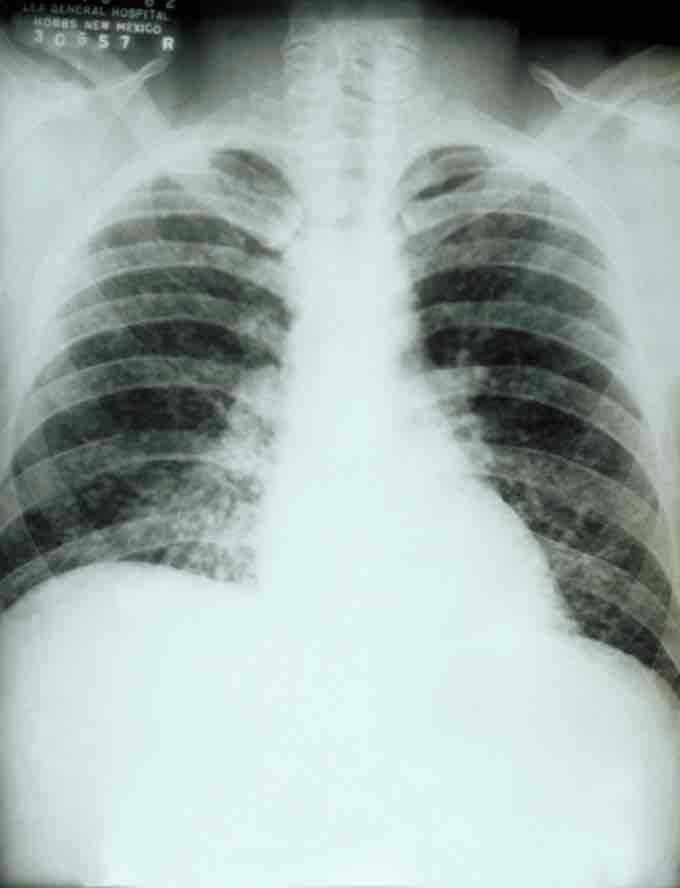

This is a chest X-ray of a patient with acute pulmonary histoplasmosis.

If symptoms of histoplasmosis infection occur, they will start within 3 to 17 days after exposure, with the average being 12 to 14 days. Most affected individuals have clinically silent manifestations and show no apparent ill effects. The acute phase of histoplasmosis is characterized by non-specific respiratory symptoms, often cough or flu-like. Chest X-ray findings are normal in 40 to 70% of cases. Chronic histoplasmosis cases can resemble tuberculosis, and disseminated histoplasmosis affects multiple organ systems and is fatal unless treated.